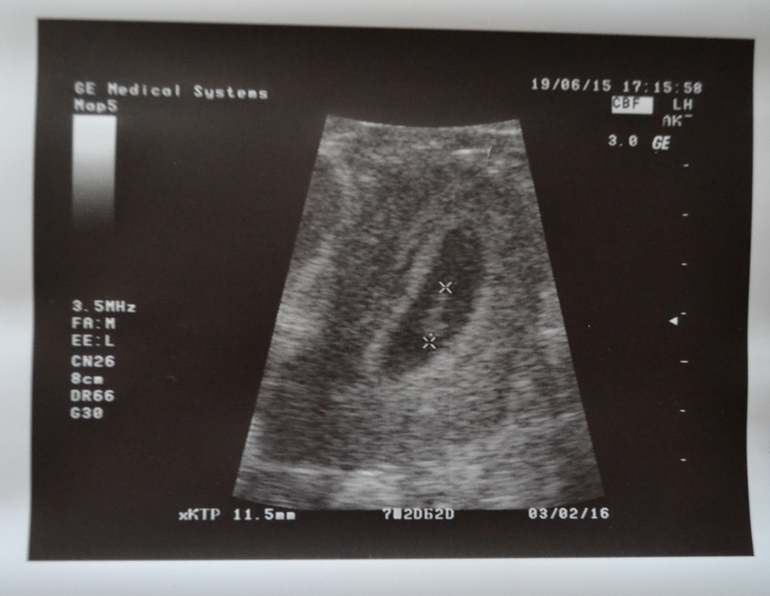

и последняя фотка нашего малышика:

По результатам :беременность прогрессирующая,без угроз,все идеально,плод есть,сердцебиение тоже)) Саламатина сказала оставить только фольку)